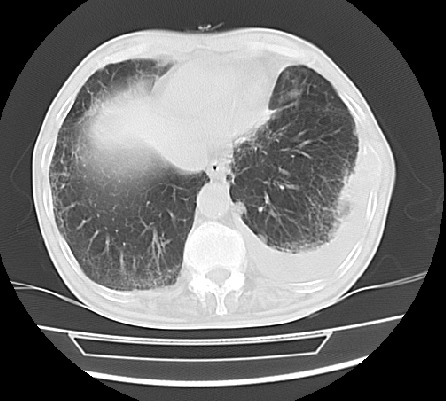

以下是引用ct诊断高手在2009-5-29 13:50:00的发言:[br]考虑左侧中央型肺癌,阻塞性肺炎伴肺不张。纵隔淋巴结转移。慢支 肺间质纤维化肺气肿。左侧胸腔积液。左侧肋骨转移?

以下是引用hhcckk在2009-5-29 14:58:00的发言:[br]左上周围型肺癌,左肺门、纵隔淋巴结转移,左侧胸腔积液,左侧肋骨转移[br]